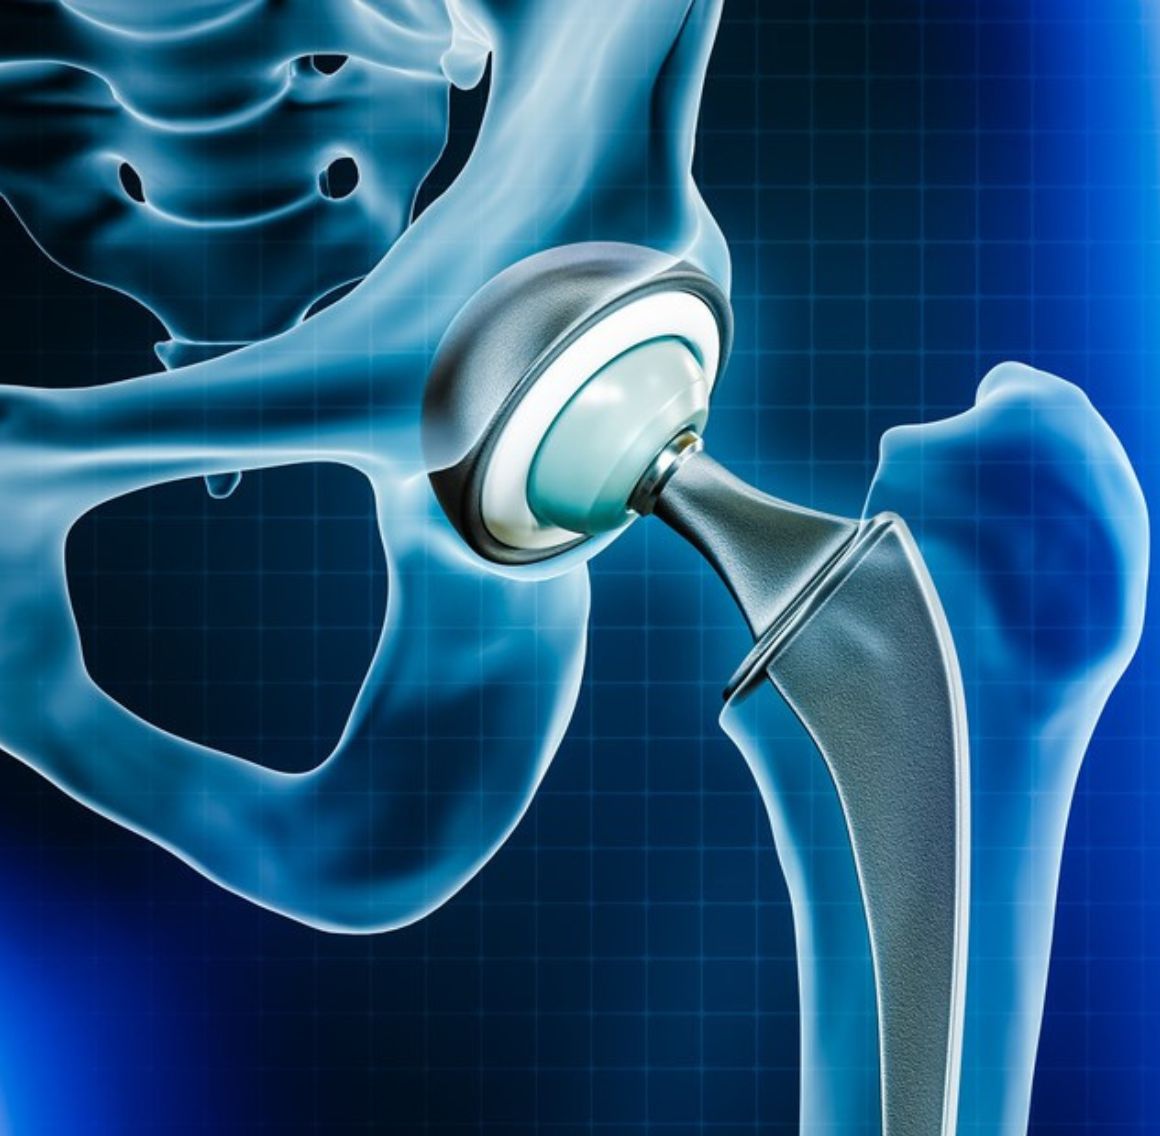

Hip Replacement Surgery involves removing the damaged or worn portions of the hip joint and replacing them with artificial components. This advanced procedure is designed to relieve chronic pain, improve mobility, and enhance overall quality of life. It is highly recommended for patients suffering from severe arthritis, hip fractures, or other debilitating hip conditions that do not respond to conservative treatments.

- Custom Implant Selection: Tailored prosthetic implants are chosen based on your anatomy and lifestyle needs, ensuring optimal joint function and longevity.